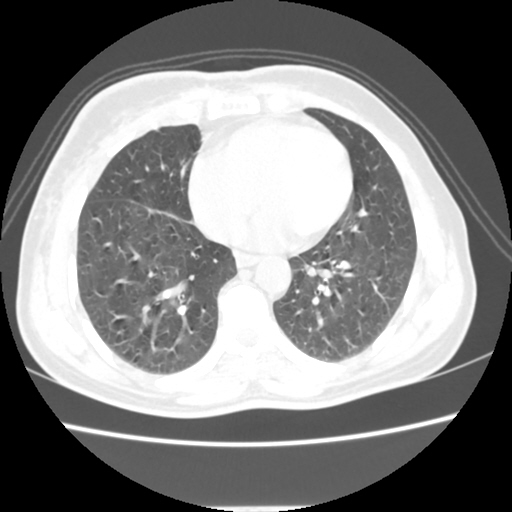

A 62 years old man with enlarged mole on chest since 2 months.

CT chest :-